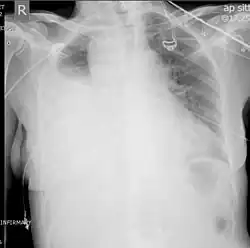

A chest X-ray is the most common technique used to diagnosis a hemothorax.[23] X-rays should ideally be taken in an upright position (an erect chest X-ray), but may be performed with the person lying on their back (supine) if an erect chest X-ray is not feasible. On an erect chest X-ray, a hemothorax is suggested by blunting of the costophrenic angle or partial or complete opacification of the affected half of the thorax. On a supine film the blood tends to layer in the pleural space, but can be appreciated as a haziness of one half of the thorax relative to the other.[5] A small hemothorax may be missed on a chest X-ray as several hundred milliliters of blood can be hidden by the diaphragm and abdominal viscera on an erect film. Supine X-rays are even less sensitive and as much as one liter of blood can be missed on a supine film.[24]

Chest MRI showing a hemothorax in a 16-day-old infant